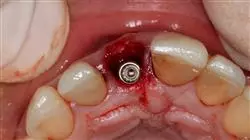

学习本课程,你将能掌握种植诊断材料和印模技术的最新发展"

参加由牙科顶级专业人士讲授的最佳美学种植大师班"